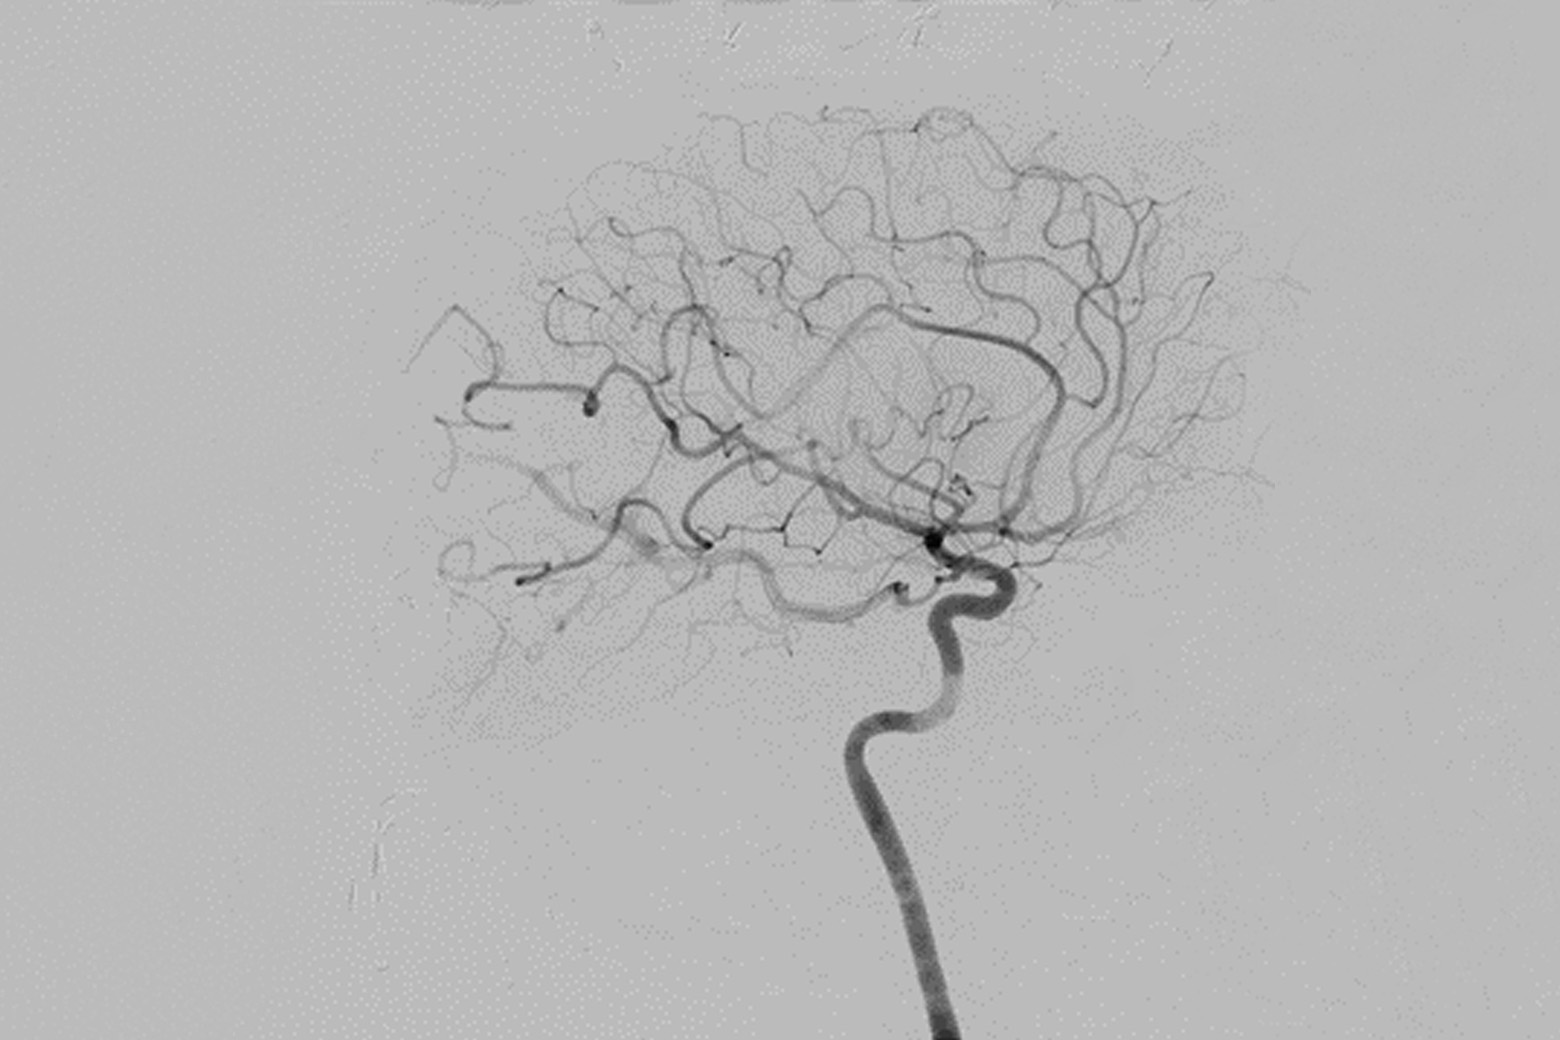

The following day, Dr. Riina performed an image-guided craniotomy and resection of the AVM. Intraoperative angiography confirmed the prior embolization and the successful resection of the remaining components of the AVM body (Slide 4). The patient’s migraines and visual field defects fully resolved after his surgery.